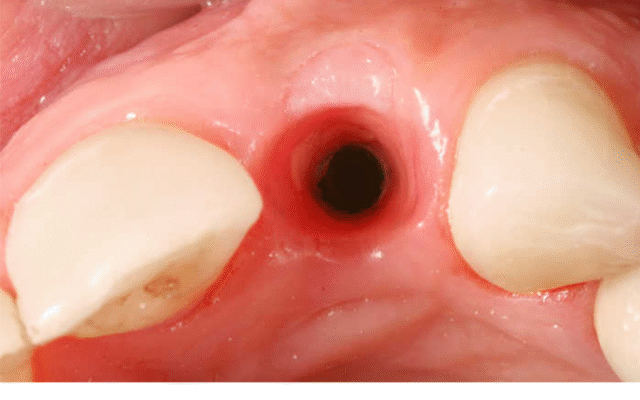

Скільки може кровити зуб після видалення?

Зазвичай кров зупиняється за пару годин. Досвід же каже — іноді трохи довше. Червона слина не означає катастрофу. Паніка тут зайва.

Отже, 24 години минуло, але все ще трохи кровить? Не боїмося. Але слід бути пильними. Правильний догляд — успіх.